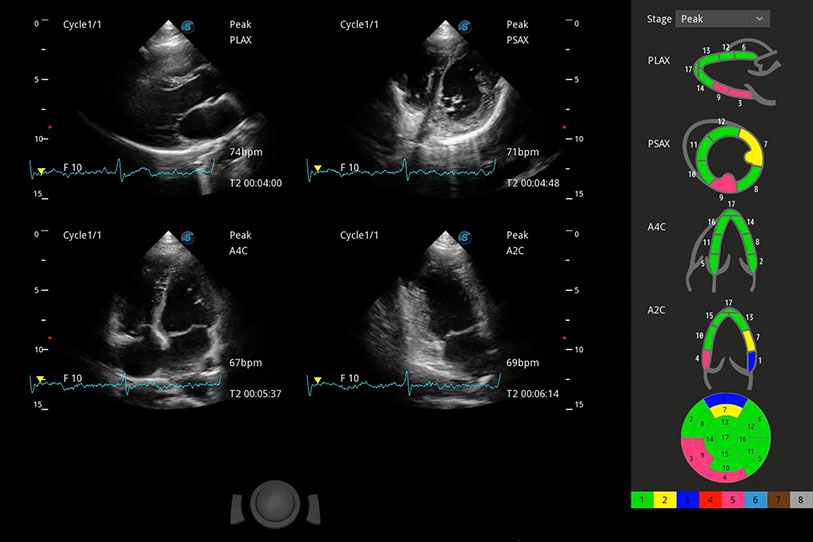

具備多種協(xié)議可選,同時(shí)支持17階段劃分法和專業(yè)的SE報(bào)告。